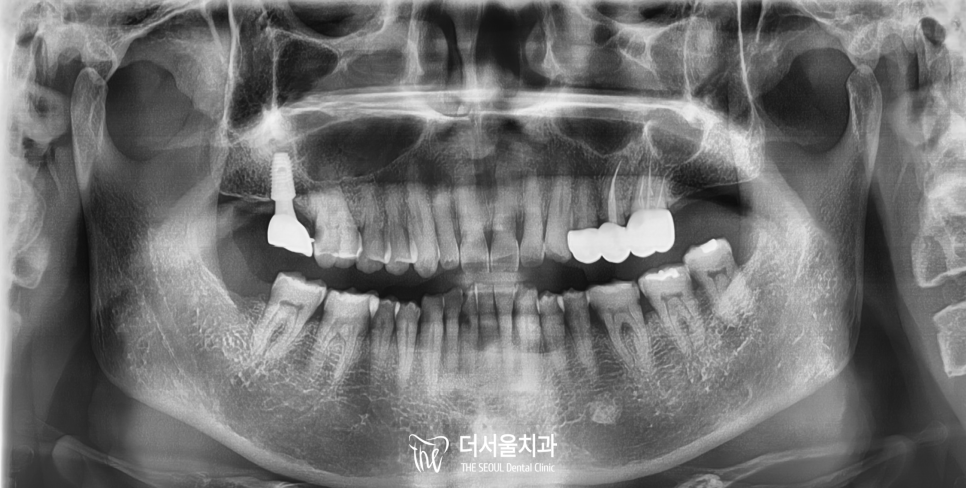

구강 전반의 현황을 확인하기 위해

이어서 Panorama X-Ray 촬영을

진행하였습니다.

파노라마 엑스레이에서

염증이나 병소는 주변보다 어둡게 나타납니다.

우선 부러진 어금니를 들여다보겠습니다.

다행스럽게도, 뿌리를 지지하던

치주 인대 일부를 제외하면

염증 등 추가 손상은 없었습니다.

깊은 부위의 큰 손상을 우려하였으나

다행스럽게도 오늘 환자께서는

어금니가 부러진 것을 깨닫자마자

저희 성남 치과 를 찾아주셨기 때문에

우식이나 염증이 없이

신속하게 처치할 수 있다는 소견입니다.

바로 옆 어금니는

깨진 부분이 치수에 인접하여

병소가 퍼지기 시작하고 있었습니다.